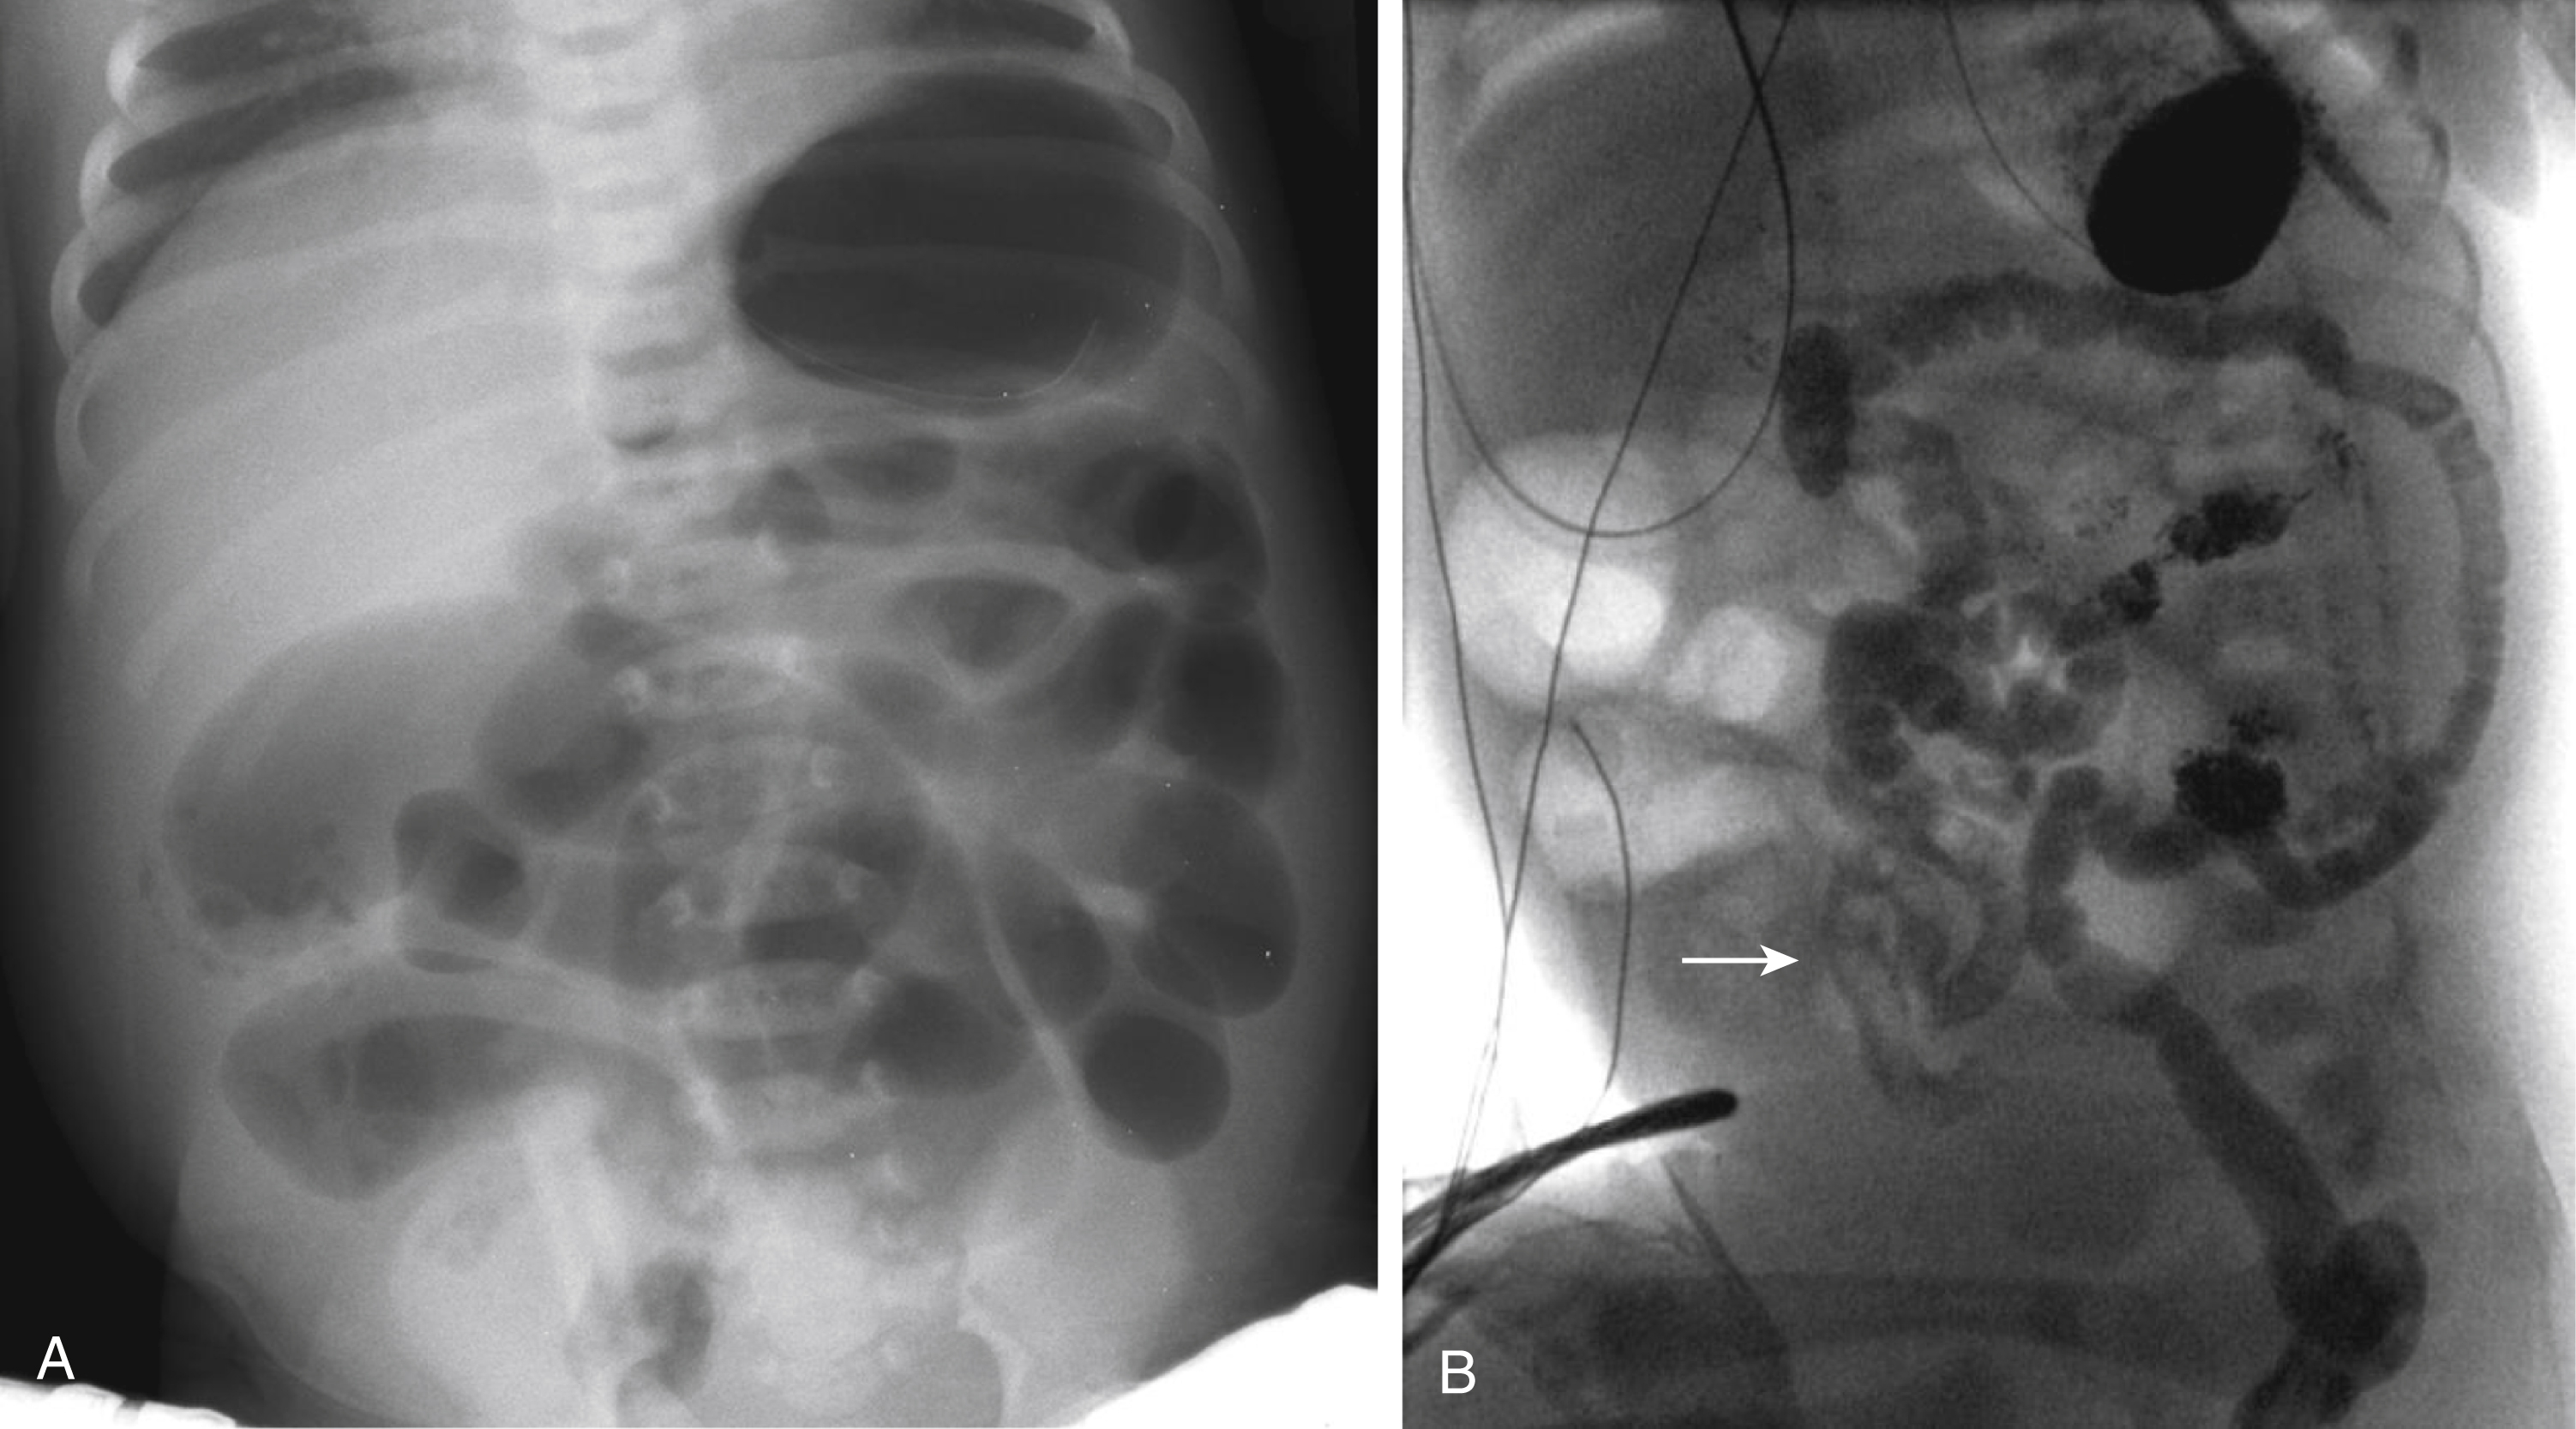

If the initial radiograph demonstrates distal obstruction with multiple dilated loops of bowel ( Fig. 4.9 ), a contrast enema is indicated to determine the cause. If meconium has already been passed, the differential diagnosis includes Hirschsprung disease, jejunal atresia, and ileal or colonic stenosis; if meconium has not been passed, the differential also includes ileal/colonic atresia, meconium ileus, functional immaturity of the colon, and imperforate anus. Imperforate anus with a fistula may allow passage of minimal meconium, and thus imperforate anus can sometimes be missed without careful physical examination.

Fig. 4.9, Distal obstruction.